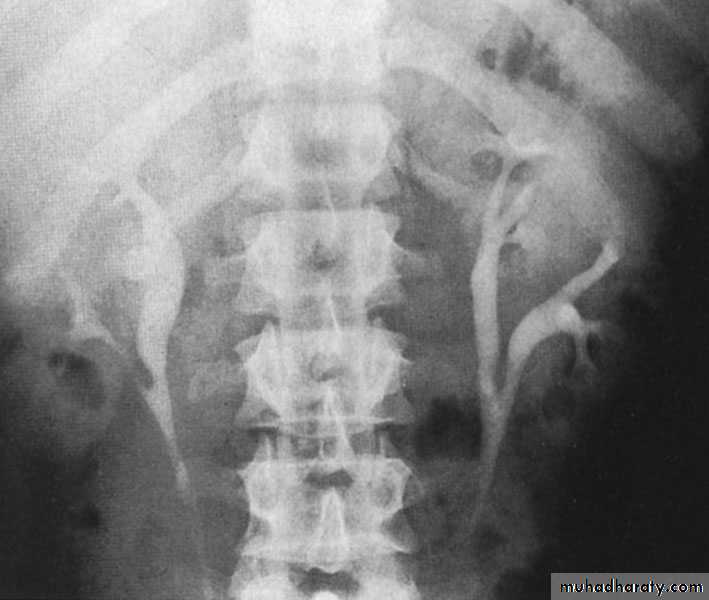

Ureteropelvic Junction (UPJ)(PUJ) Obstruction (stenosis)

Urology

The most common cause of significant dilation of the collecting system in the fetal kidney

Boys > Girls

Left-sided lesions predominate

15% bilateral

ETIOLOGY

Intraluminal : mucosal fold that causes valve

like effect.

Intrinsic (intramural) interruption in the

development of the circular musculature of the UPJ

Extrinsic An aberrant, accessory, or early-branching

lower-pole renal artery

SYMPTOMS/PRESENTATION

Most infants are asymptomatic and most children are discovered because of their symptoms

Episodic flank or upper abdominal pain, sometimes associated with nausea and vomiting

DIAGNOSIS

U/S: hydronephrosis

IVU: diagnostic , hydronephrosis with

fixed stenotic segment or complete

obstruction

CT scan: hydronephrosis that ends